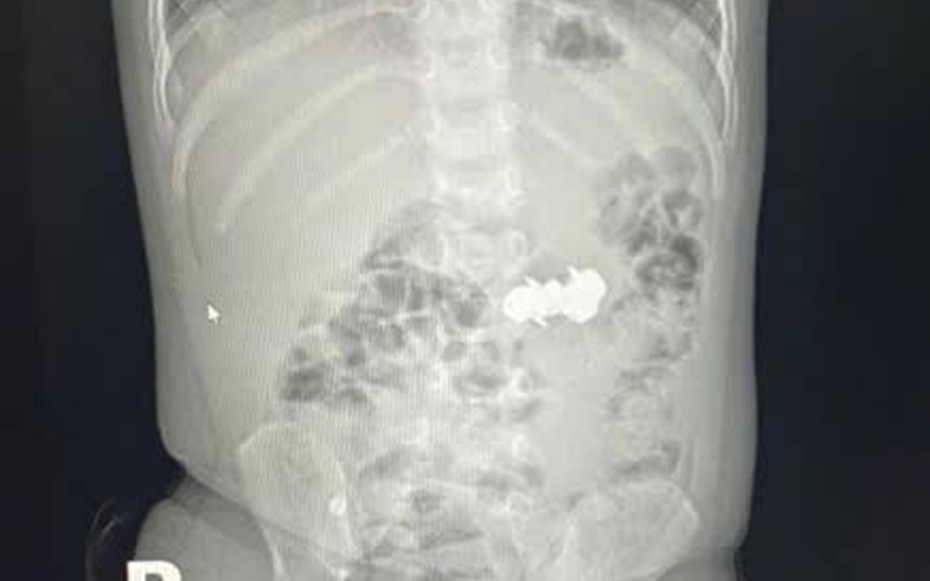

Bé D.H.P. (2 tuổi, trú tại Nghệ An) được gia đình đưa đến viện trong tình trạng nghi ngờ nuốt dị vật trong lúc chơi đồ chơi. Kết quả chụp X-quang bụng cho thấy trong ổ bụng có bốn dị vật kim loại nhỏ hình tròn, có đầu nhọn, nghi là đinh nam châm. Các viên nam châm này đã hút dính nhau trong đường tiêu hoá, tạo nên nguy cơ đặc biệt nghiêm trọng.

Tại Khoa Cấp cứu tổng hợp, các bác sĩ tiến hành thăm khám lâm sàng và chỉ định các cận lâm sàng cần thiết, trong đó có thực hiện chụp X-Quang có cản quang vùng bụng.

Hình ảnh ghi nhận có dị vật cản quang dạng chuỗi nằm ở vùng bụng quanh rốn và hố chậu phải. Các bác sĩ đã hội chẩn liên khoa và thống nhất thực hiện phẫu thuật nội soi ổ bụng cấp cứu.